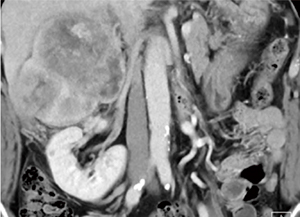

右副腎腫瘍摘出の栄養血管推定術前シミュレーションとして,造影CT,腹部アンギオを行った。アンギオの結果,副腎腫瘍には右横隔膜下動脈,右肝動脈からの分岐右副腎動脈,腰動脈などから多数の栄養が認められた(図1)。さらに,右腎動脈遠位付近より副腎腫瘍に上行する血管を確認したため,右腎動脈を選択造影したが(図2),どこから分岐しているのかアンギオ,造影CTのVR処理,MIP画像,MPR画像のいずれでも推定が困難であった(図3,4)。

図4 造影CT:VR MPR表示,コロナル画像 |